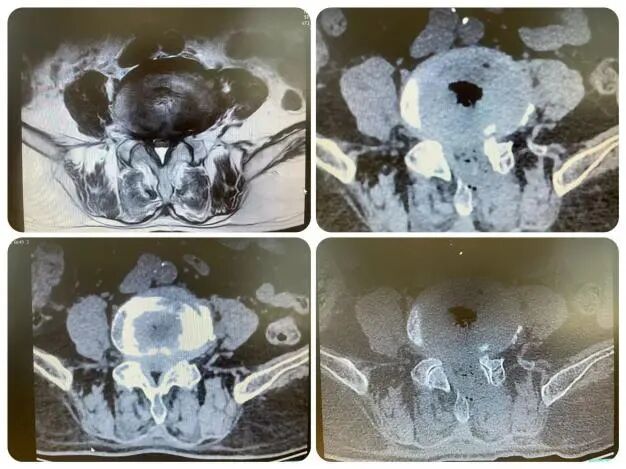

今年50岁的市民姚先生,腰腿疼痛已经一年多了,一直保守治疗,但效果不理想,总是反复发作,近期疼痛加重,稍走几步就感到下肢麻木剧痛,导致卧床不起,生活无法自理,苦不堪言。姚先生来到了邓州市人民医院骨外科三病区就诊。经过系统检查,姚先生腰5棘突叩击疼阳性,左下肢拖拽步态,踝关节背伸无力,小腿后方痛觉过敏,直腿抬高试验强阳性。 诊断为:1.腰5骨骶1椎间盘突出伴坐骨神经痛。核磁检查显示:腰椎退行性改变;L3—4、L4—5椎间盘膨出;L5S1椎间盘脱出(偏左);腰椎后方棘间筋膜炎。